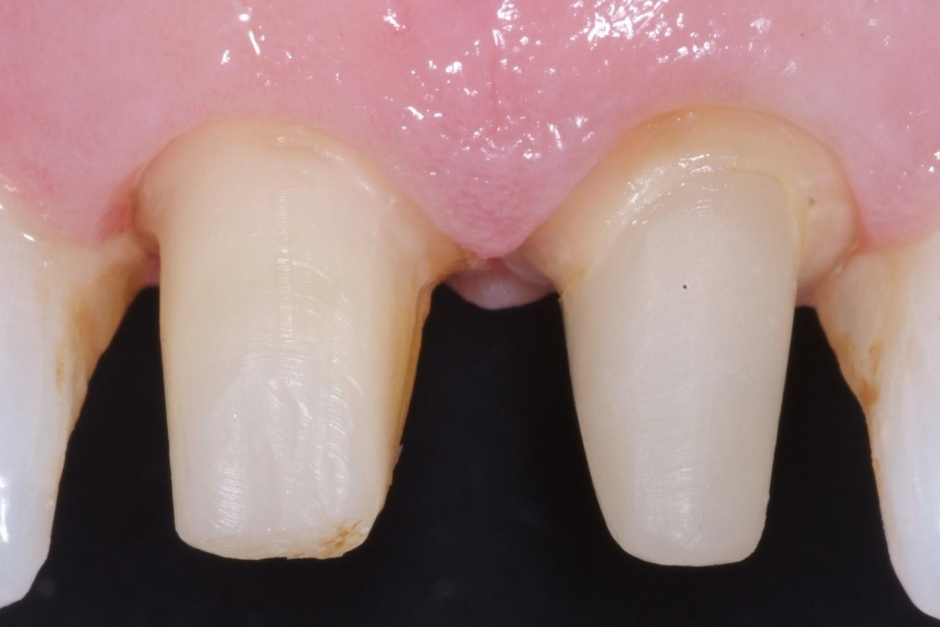

What happens if you have a case like the one below where you have preps and implants?

This is an example of a bigger case – one where we wanted to be able to incorporate the fixture position of the implants into the model.

You can see in the series of images below, courtesy of Ashley Bryne, how we did this.

So now we had the benefits we were seeing with routine work and in our implant cases/combined cases.